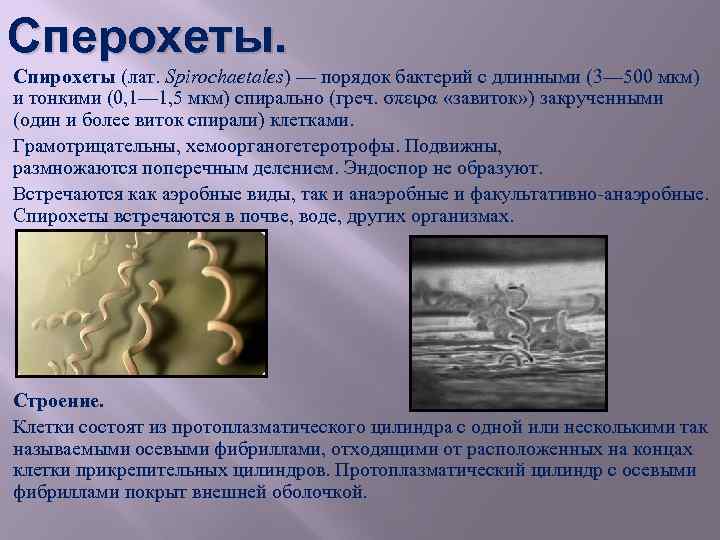

Лептоспиры: фотографии удивительных микроорганизмов